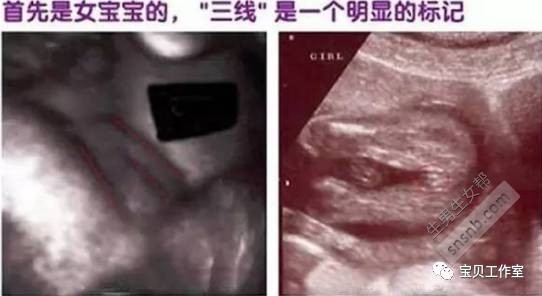

言归正传,先抛开是否靠谱不谈,判定宝宝性别,光是民间的土方就有很多。其实最直观简单准确的方法就是B超的图像和数据了。

这个时候,掌握这个B超图片简单的判断方法,以及和医生巧妙的谈话技巧之后,那综合起来就可以猜个八九不离十了。

下面分享B超图像背后的秘密,我的怀孕症状,以及B超检查时医生给我的暗示语(二胎开放前)。